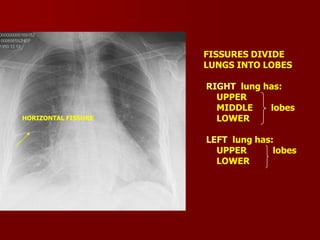

FISSURES DIVIDE

LUNGS INTO LOBES

HORIZONTAL FISSURE

RIGHT lung has:

UPPER

MIDDLE

lobes

LOWER

LEFT lung has: